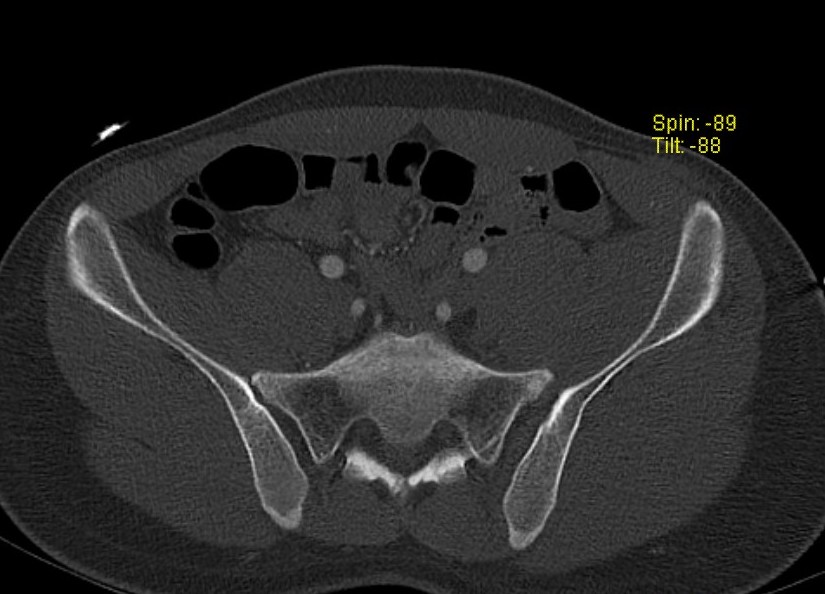

CT scan

X-rays

Inlet view

- 40o caudal

- shows AP displacement of sacrum and anterior ring

- anterior and posterior sacral borders

Outlet view

- 40o cephalad

- vertical displacement of sacrum relative to ilium